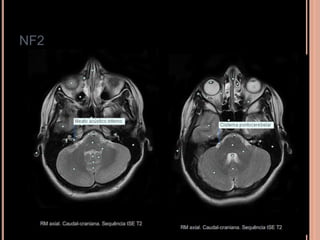

NF2

 Schwannomas vestibulares:

Originam-se no conduto auditivo interno; pode se

estender para a cisterna pontocerebelar;

o 5° par (trigêmio): 2° sítio mais acometido;

Achados de imagem NF2

 Schwannomas vestibulares (realce homogêneo

pelo contraste, seria hipo em T1)

 Meningeomas (realce intenso pelo contraste)

 Calcificação assimétrica de plexo corióide

 Schwannomas volumosos se estendendo para a

cisterna pontocerebelar com intensa impregnação

pelo Gd; na sequência em T2 tem hipersinal

heterogêneo;

 Múltiplos nódulos, em T1 pós contraste importante

realce compatíveis com schwannomas;

SCWHANNOMAS

Pequenas lesões no CAI, bem mais caracterizada

nas aquisições volumétricas(3D CISS);

Aspecto de “sorvete de casquinha” quando lesões

maiores com extensão pontocerebelar;

Hipo em T1 e hiper heterogêneo em T2;

Impregnação pelo Gd homogênea se pequenos e

heterogênea se grandes;

RM